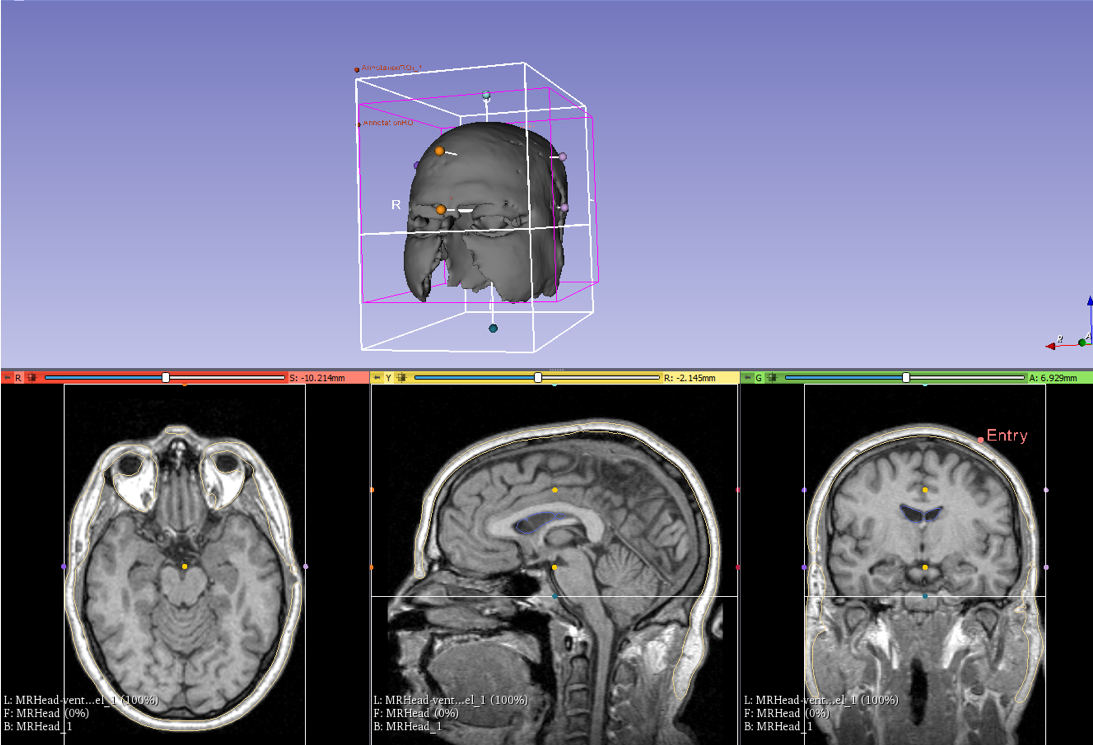

courses:456:2019:projects:456-2019-15:segmentation.png

segmentation.png